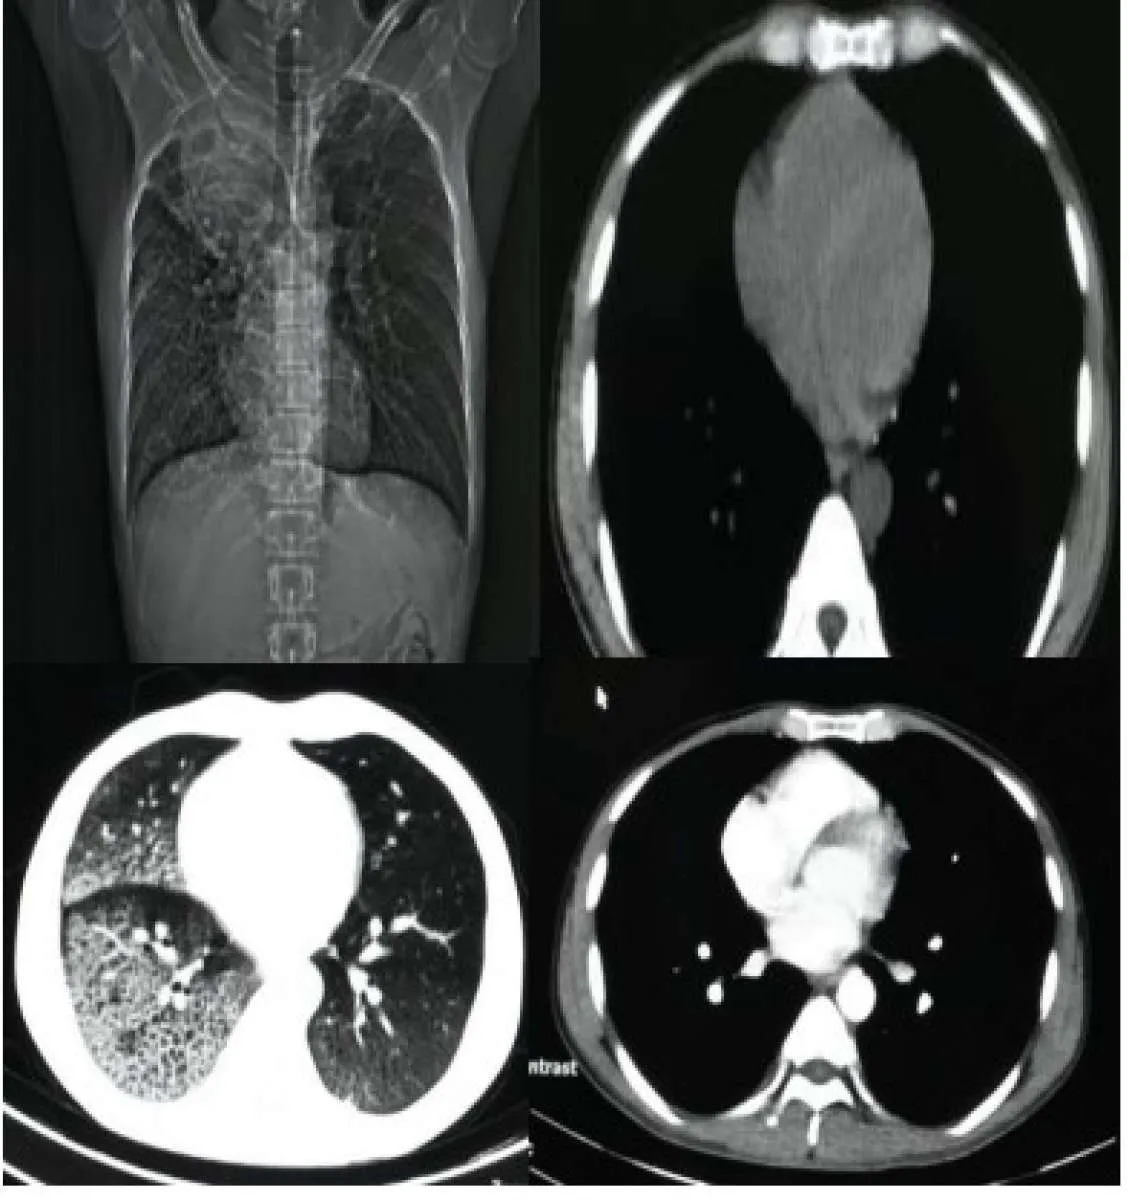

2. Peralatan rontgen thorax, CT scan.